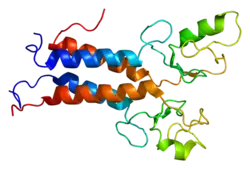

Protein structure

The BRCA1 protein contains the following domains:[26]

- Zinc finger, C3HC4 type (RING finger)

- BRCA1 C Terminus (BRCT) domain

This protein also contains nuclear localization signals and nuclear export signal motifs.[27]

The human BRCA1 protein consists of four major protein domains; the Znf C3HC4- RING domain, the BRCA1 serine domain and two BRCT domains. These domains encode approximately 27% of BRCA1 protein. There are six known isoforms of BRCA1,[28] with isoforms 1 and 2 comprising 1863 amino acids each.

BRCA1 is unrelated to BRCA2, i.e. they are not homologs or paralogs.[10]

Zinc ring finger domain

The RING motif, a Zn finger found in eukaryotic peptides, is 40–60 amino acids long and consists of eight conserved metal-binding residues, two quartets of cysteine or histidine residues that coordinate two zinc atoms.[30] This motif contains a short anti-parallel beta-sheet, two zinc-binding loops and a central alpha helix in a small domain. This RING domain interacts with associated proteins, including BARD1, which also contains a RING motif, to form a heterodimer. The BRCA1 RING motif is flanked by alpha helices formed by residues 8–22 and 81–96 of the BRCA1 protein. It interacts with a homologous region in BARD1 also consisting of a RING finger flanked by two alpha-helices formed from residues 36–48 and 101–116. These four helices combine to form a heterodimerization interface and stabilize the BRCA1-BARD1 heterodimer complex. Additional stabilization is achieved by interactions between adjacent residues in the flanking region and hydrophobic interactions. The BARD1/BRCA1 interaction is disrupted by tumorigenic amino acid substitutions in BRCA1, implying that the formation of a stable complex between these proteins may be an essential aspect of BRCA1 tumor suppression.[30]

The ring domain is an important element of ubiquitin E3 ligases, which catalyze protein ubiquitination. Ubiquitin is a small regulatory protein found in all tissues that direct proteins to compartments within the cell. BRCA1 polypeptides, in particular, Lys-48-linked polyubiquitin chains are dispersed throughout the resting cell nucleus, but at the start of DNA replication, they gather in restrained groups that also contain BRCA2 and BARD1. BARD1 is thought to be involved in the recognition and binding of protein targets for ubiquitination.[31] It attaches to proteins and labels them for destruction. Ubiquitination occurs via the BRCA1 fusion protein and is abolished by zinc chelation.[30] The enzyme activity of the fusion protein is dependent on the proper folding of the ring domain.

Serine cluster domain

BRCA1 serine cluster domain (SCD) spans amino acids 1280–1524. A portion of the domain is located in exons 11–13. High rates of mutation occur in exons 11–13. Reported phosphorylation sites of BRCA1 are concentrated in the SCD, where they are phosphorylated by ATM/ATR kinases both in vitro and in vivo. ATM/ATR are kinases activated by DNA damage. Mutation of serine residues may affect localization of BRCA1 to sites of DNA damage and DNA damage response function.[29]

BRCT domains

The dual repeat BRCT domain of the BRCA1 protein is an elongated structure approximately 70 Å long and 30–35 Å wide.[32] The 85–95 amino acid domains in BRCT can be found as single modules or as multiple tandem repeats containing two domains.[33] Both of these possibilities can occur in a single protein in a variety of different conformations.[32] The C-terminal BRCT region of the BRCA1 protein is essential for repair of DNA, transcription regulation and tumor suppressor function.[34] In BRCA1 the dual tandem repeat BRCT domains are arranged in a head-to-tail-fashion in the three-dimensional structure, burying 1600 Å of hydrophobic, solvent-accessible surface area in the interface. These all contribute to the tightly packed knob-in-hole structure that comprises the interface. These homologous domains interact to control cellular responses to DNA damage. A missense mutation at the interface of these two proteins can perturb the cell cycle, resulting a greater risk of developing cancer.